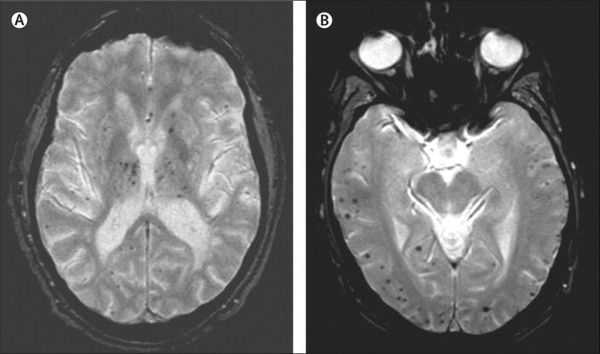

МРТ и КТ проводят для выявления поддающихся лечению причин деменции и нарушений, которые могут усугубить симптомы. Структурные изменения по данным магнитно-резонансной томографии являются более прогностически значимыми для дальнейших изменений в когнитивной сфере, чем биомаркеры цереброспинальной жидкости. По данным магнитно-резонансной томографии, признаки цереброваскулярного заболевания, такие как лейкоареоз и множественные подкорковые лакунарные инфаркты, чаще наблюдаются у пациентов с болезнью Альцгеймера, чем в контрольной группе. [7] Асимметричная атрофия медиальных отделов височной доли также не исключает сосудистую деменцию.

Описана смешанная модель патогенеза болезни Альцгеймера, которая предполагает взаимодействие церебральной амилоидной ангиопатии с сосудистыми факторами на ранних стадиях патологического процесса. Предполагается, что синергия между накоплением амилоида и цереброваскулярной патологией может инициировать дальнейшую дисфункцию нейронов и нейродегенерацию. [8] В этом отношении церебральные микрокровоизлияния, выявляемые в режиме Т2 градиентного эхо на магнитно-резонансной томографии, являются дополнительным и доступным диагностическим маркером, повышающим диагностическую значимость лейкоареоза и свидетельствующим в пользу церебральной амилоидной ангиопатии или гипертонической микроангиопатиии, особенно в случаях смешанной патологии и тяжелого когнитивного дефицита.

Локализация церебральных микрокровоизлияний является дифференциально-диагностическим признаком ведущего патологического процесса. В случае болезни Альцгеймера наблюдается корковая локализация микрокровоизлияний, в случае дисциркуляторной энцефалопатии или сосудистой деменции будут визуализироваться микрокровоизлияния в глубинных отделах мозга. [9] [10]